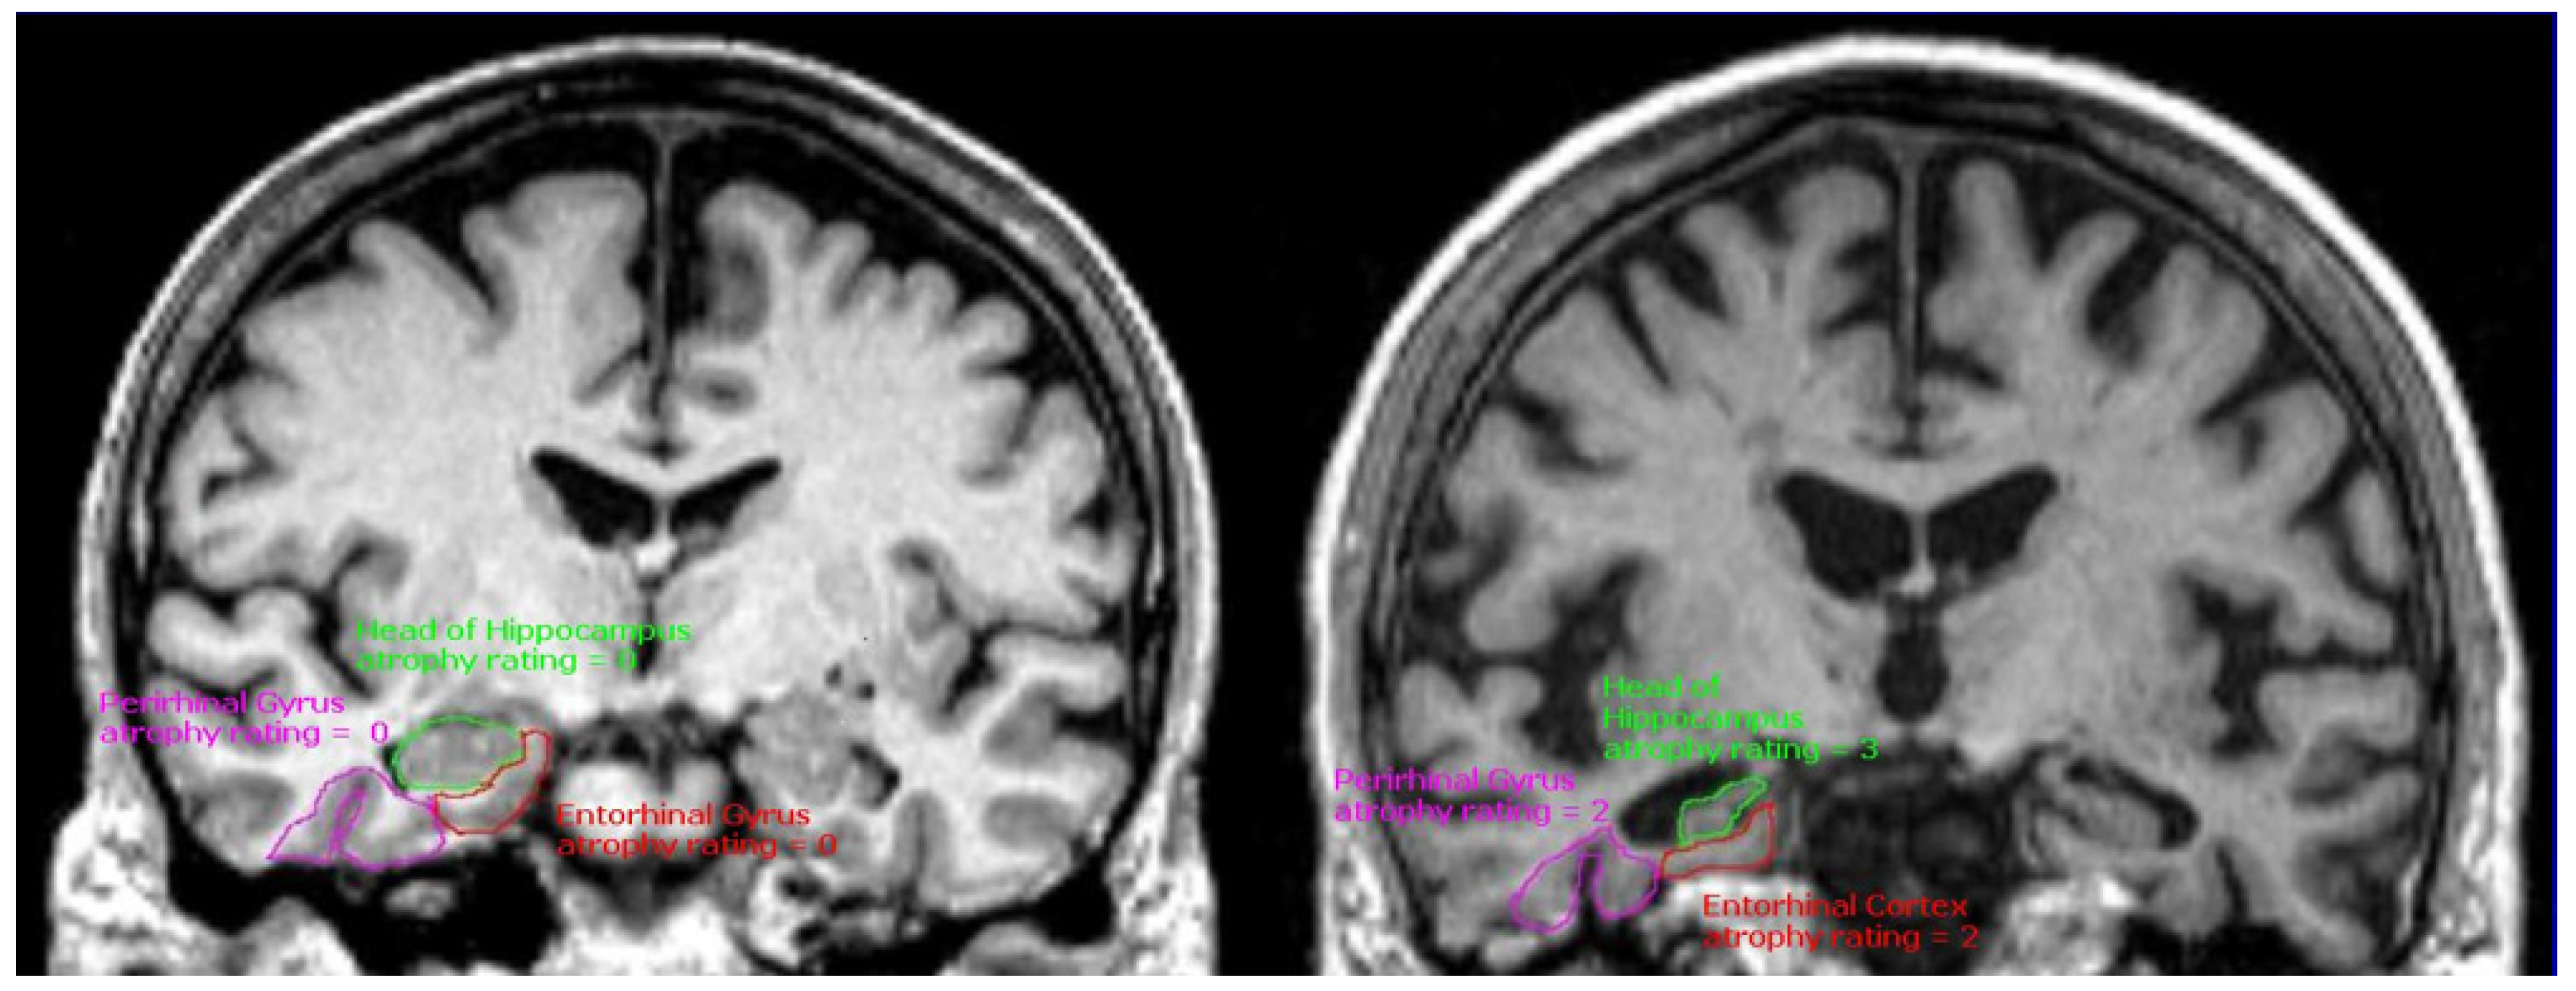

3.1. Structural MRI

- Harper, L.; Barkhof, F.; Scheltens, P.; Schott, J.M.; Fox, N.C. An algorithmic approach to structural imaging in dementia. J. Neurol. Neurosurg. Psychiatry 2013, 85, 692–698. [Google Scholar] [CrossRef] [PubMed]

- Jack, C.R.; Petersen, R.C.; Xu, Y.; O’brien, P.C.; Smith, G.E.; Ivnik, R.J.; Boeve, B.F.; Tangalos, E.G.; Kokmen, E. Rates of hippocampal atrophy correlate with change in clinical status in aging and AD. Neurology 2000, 55, 484–490. [Google Scholar] [CrossRef] [PubMed]

- Murray, M.E.; Graff-Radford, N.R.; Ross, O.A.; Petersen, R.C.; Duara, R.; Dickson, D.W. Neuropathologically defined subtypes of Alzheimer’s disease with distinct clinical characteristics: A retrospective study. Lancet Neurol. 2011, 10, 785–796. [Google Scholar] [CrossRef] [PubMed]

- Whitwell, J.L.; Dickson, D.W.; Murray, M.E.; Weigand, S.D.; Tosakulwong, N.; Senjem, M.L.; Knopman, D.S.; Boeve, B.F.; Parisi, J.E.; Petersen, R.C.; et al. Neuroimaging correlates of pathologically defined subtypes of Alzheimer’s disease: A case-control study. Lancet Neurol. 2012, 11, 868–877. [Google Scholar] [CrossRef] [PubMed]

- Risacher, S.L.; Anderson, W.H.; Charil, A.; Castelluccio, P.F.; Shcherbinin, S.; Saykin, A.J.; Schwarz, A.J.; Alzheimer’s Disease Neuroimaging Initiative; Alzheimer’s Disease Neuroimaging Initiative. Alzheimer disease brain atrophy subtypes are associated with cognition and rate of decline. Neurology 2017, 89, 2176–2186. [Google Scholar] [CrossRef] [PubMed]

- Persson, K.; Eldholm, R.S.; Barca, M.L.; Cavallin, L.; Ferreira, D.; Knapskog, A.-B.; Selbæk, G.; Brækhus, A.; Saltvedt, I.; Westman, E.; et al. MRI-assessed atrophy subtypes in Alzheimer’s disease and the cognitive reserve hypothesis. PLoS ONE 2017, 12, e0186595. [Google Scholar] [CrossRef] [PubMed]